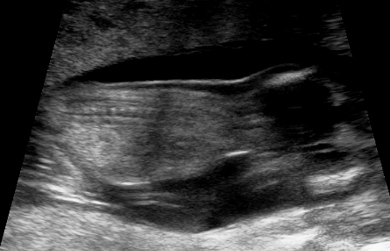

Guesses anyone? Was told boy at 12w2dAttachment 18706Attachment 18707Attachment 18708

Too early for a potty shot, and I don't see a nub. But I don't see anything obvious in the potty shot, so slight girl lean.

No nub, can't go by potty shot.

I can't see anything. Sweet little bub putting his/ her legs up! Wants to keep it a surprise for a bit longer!